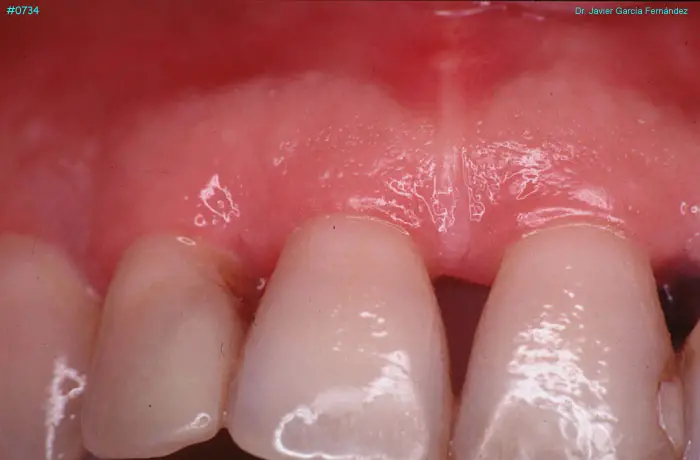

Atlas of Surgical Techniques in Periodontics. Chapter III. Atlas de Técnicas Quirúrgicas en Periodoncia